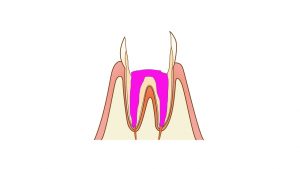

いよいよドックベストセメントを使用した治療法です。

削らない、と言われていますが実際には虫歯の部分を少し削ります。歯と詰め物が接着する部分に虫歯が残っているとそこに隙間ができて虫歯が再発してしまうからです。しかし、健康な歯についてはほとんど削らない為、痛みが出ることが少なく麻酔をすることはほとんどありません。

必要最低限の虫歯除去の後ドックベストセメントを充填し(または塗布)その上にCR充填を行います。もともとインレー形成されていた歯の場合は、ドックベストセメントの塗布後セラミックスのインレーを入れます。